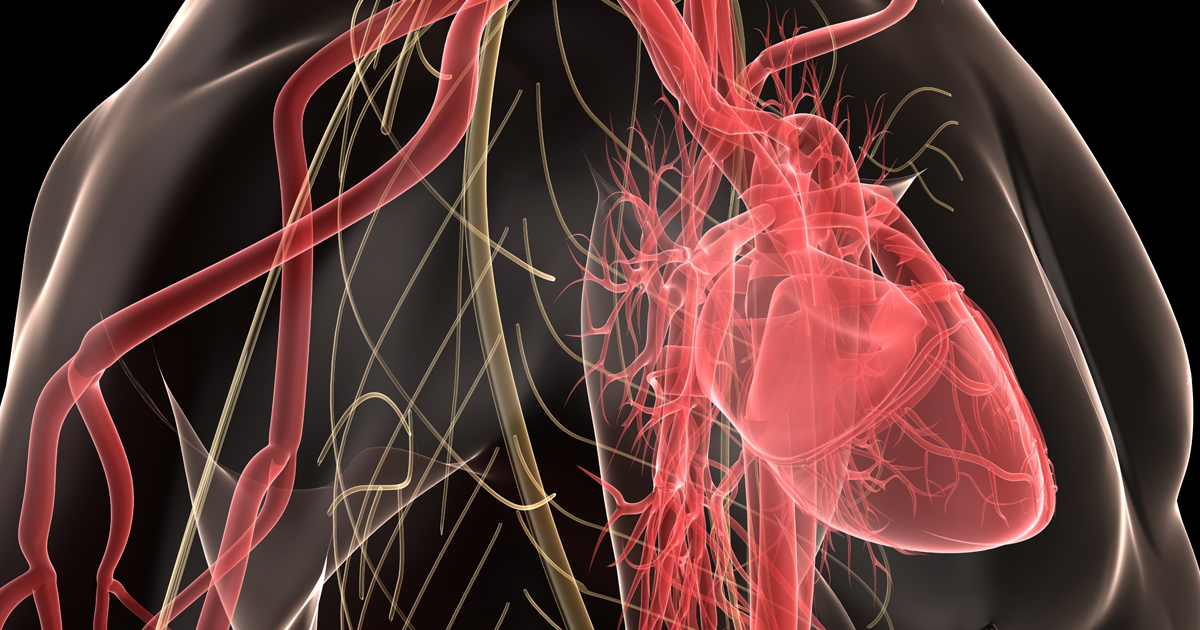

大特価 pop | 心臓CT活用マニュアル 治療戦略に活かす! 華岡 真鍋 慶一, 医学一般

大特価 pop | 心臓CT活用マニュアル 治療戦略に活かす! 華岡 真鍋 慶一, 医学一般

治療戦略に活かす! 心臓CT活用マニュアル | 華岡 慶一, 真鍋,

治療戦略に活かす! 心臓CT活用マニュアル | 華岡 慶一, 真鍋, 81qKL64RHHL._AC_UF1000,,

81qKL64RHHL._AC_UF1000,, 冠動脈CT検査におけるGEの最新技術-技術解説 - GEヘルスケア,

冠動脈CT検査におけるGEの最新技術-技術解説 - GEヘルスケア, 冠動脈疾患疑い患者への検査、CT vs.侵襲的冠動脈造影/NEJM,

冠動脈疾患疑い患者への検査、CT vs.侵襲的冠動脈造影/NEJM, ここから始める循環器疾患のCT・MRI (画像診断BOOKS) | 似鳥俊明